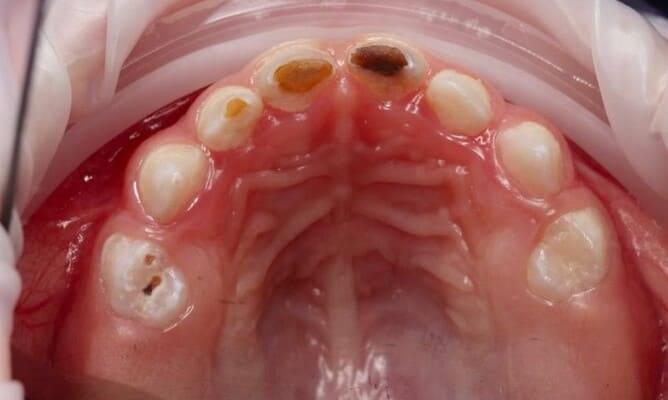

Один рік і два місяці вік дитини. Хтось скаже: «Що там тим зубам можна лікувати?!» Однак є ситуації, коли каріозний процес розвивається просто блискавично. Часто це пов’язано з порушеннями у формуванні твердих тканин ще внутрішньоутробно. А коли такі зубчики прорізуються, руйнування відбувається просто «на очах». Вісім із восьми зубів уражені, а 4 з них потребують часткового видалення пульпи («нерва»). На цьому етапі зуби вже починають турбувати і не зважаючи на юний вік дитини, зволікати не можна. Завдяки високій компетенції наших анестезіологів, які працюють з дітьми від самого народження і навіть з передчасно народженими, ми можемо проводити відповідне лікування в анестезіологічному забезпеченні за потреби навіть з першого зуба. Верхнім зубчикам, які сильно уражені, служити до 7-8 років, тому вони покриваються стандартними естетичними цирконієвими коронками, які дають максимальний результат по надійності, функції та естетиці. Година з половиною роботи і дитина може знову кусати без болю і дискомфорту. Важливо пам’ятати: для лікування зубів ніколи не буває “зарано”, це потрібно робити тоді, коли є відповідні показання